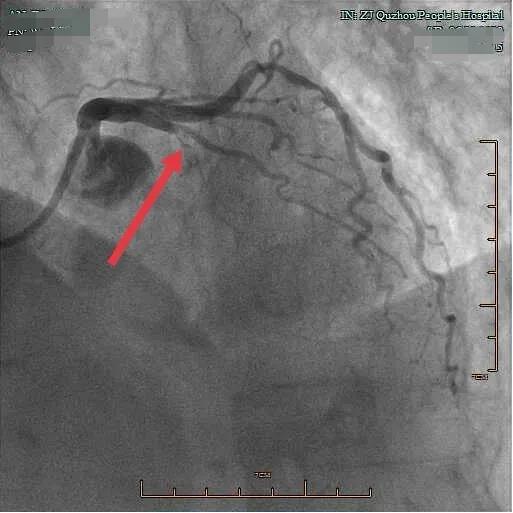

據悉,今年已有94歲高齡的吳老太太突發心臟疼痛,是由于老太太的冠脈血管有多處狹窄,最嚴重處已完全堵塞,這是造成老太太心肌梗死的病灶?!肮呐K血液的血管,就像自來水管,長期使用就可能會有雜質堵塞。經皮冠狀動脈造影術,就是明確供應心臟血液的血管是否堵塞,堵塞了多少?!毙膬瓤浦魅瓮罆曾Q醫師告知。

急診手術準備就緒,在屠曉鳴的帶領下,心內科介入診療團隊為吳老太太行急診經皮冠狀動脈造影術。

橈動脈穿刺建立通路后,支架植入病變狹窄的血管,定位明確,立即使用抽吸導管抽出長條狀血栓,快速打通了血管,順利在最嚴重狹窄處植入支架,手術成功!